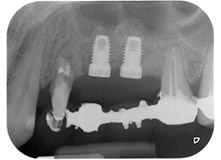

Eine 58-jährige Patientin, die auch eine gute Freundin und ärztliche Kollegin ist, beschwerte sich über Schmerzen und erhöhte Beweglichkeit ihres Brückenpfeilers 24. Es lag auch eine parodontale Entzündung vor, mit Taschentiefen von 7 mm mesiobukkal und mehr als 12 mm distal und einer Furkationsbeteiligung dritten Grades. Darüber hinaus zeigte die Röntgenaufnahme eine großflächige apikale Aufhellung am endodontisch (alio loco) vorbehandelten Zahn 24 (Abb. 1).

Ein Jahr zuvor waren die Zähne 25 und 26 vor dem Einsetzen der Brücke aufgrund traumatischer und endoparodontaler Ursachen extrahiert worden. Eine Paro-Endo-Läsion wurde bei unklarer ätiologischer Hauptkomponente für den Zahn 24 diagnostiziert. Die Patientin machte deutlich, dass sie ihre Pfeilerzähne 24 und 27 behalten und keinen endgültigen oder temporären herausnehmbaren Zahnersatz akzeptieren will. Darum wurde vereinbart, alles zu versuchen, beide Zähne, trotz der nach den radiologischen und klinischen Befunden als schlecht einzustufenden Prognose, zu erhalten.